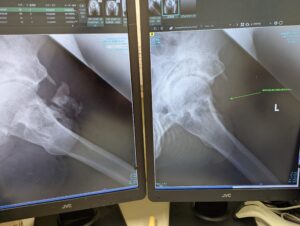

レントゲンは直ぐに呼ばれて、臥位と立位で合計3枚撮影。

- 異所性骨化巣の再発はなし